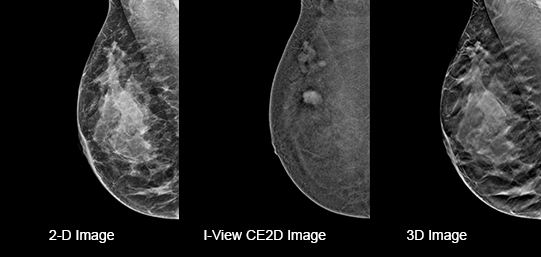

Hologic Selenia® Dimensions, tek bir tarama işleminde hem 2D dijital mamografi hem de gelişmiş 3D tomosentez teknolojisini bir arada sunar. Bu yenilikçi yaklaşım, radyologların meme dokusunun detaylarını daha eksiksiz değerlendirmesine olanak tanır ve teşhis doğruluğunu artırır. C-View™ sentezlenmiş 2D görüntü teknolojisi sayesinde, radyasyon dozu analog mamografi seviyelerine çekilirken, görüntü kalitesinden ödün verilmez. Bu özellik, özellikle yoğun meme dokusuna sahip hastalarda yüksek tanı güvenilirliği sağlar ve erken kanser tespitinde kritik rol oynar.

Hologic Selenia® Dimensions, C-View™ sentetik 2D görüntüleme teknolojisi sayesinde, 3D tomosentez verilerinden oluşturulan yüksek kaliteli 2D mamografi görüntüleri sağlar. Bu yöntem, geleneksel çiftli tarama yerine tek bir 3D tarama ile hem 3D hem de 2D görüntü elde edilmesini mümkün kılarak radyasyon dozunu önemli ölçüde azaltır. Klinik çalışmalarda, C-View™ teknolojisiyle radyasyon dozu %40-50 oranında düşürülürken, görüntü kalitesi ve tanı güvenilirliği korunmuştur. Böylece hastalar daha az radyasyon riskiyle erken ve doğru teşhis imkanına kavuşur.

iView Contrast Enhanced , Hologic’in 3D mamografi platformlarına entegre edilebilen, kontrast madde destekli bir görüntüleme yazılımıdır. Bu teknoloji, damarlanma artışı gösteren lezyonları klasik görüntüleme tekniklerine göre çok daha belirgin hale getirerek malignite şüphesi taşıyan dokuların daha net değerlendirilmesini sağlar. Dinamik kontrast yapısıyla, anjiyografi benzeri bir görüntüleme elde edilir; bu sayede hem morfolojik hem de fonksiyonel bilgi birlikte sunulur.

Özellikle yoğun meme yapısına sahip ya da klasik mamografi ve ultrason ile net sonuç alınamayan olgularda, iView CE, manyetik rezonans (MR) alternatifi olarak tercih edilebilir. Hologic’in özel yazılım algoritmaları sayesinde düşük dozda kontrast ile yüksek duyarlılıkta tarama yapılabilir.

Intelligent 2D™, Hologic’in 3D tomosentez verilerini kullanarak yüksek kaliteli sentetik 2D görüntüler oluşturan gelişmiş bir görüntüleme teknolojisidir. Bu teknoloji sayesinde, ayrı bir 2D çekim yapmaya gerek kalmadan tanısal değeri yüksek 2D görüntüler elde edilir. Böylece hem radyasyon dozu azaltılır hem de hastaya ikinci bir çekim uygulanmasına gerek kalmaz.

Gelişmiş algoritmalar, her taramada ayrıntılı veri analizi yaparak klasik 2D görüntülere eşdeğer ya da daha üstün nitelikte sonuçlar sunar. Ayrıca, bu teknoloji sayesinde veri boyutları küçülür, görüntüler daha hızlı işlenir ve radyologların değerlendirme süresi kısalır.